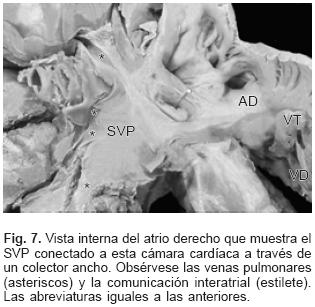

En la CATVP al atrio derecho el SVP se integra en la parte posterosuperior de esta cámara a través de un colector muy corto (Fig. 7). En el sitio de conexión al seno venoso coronario el colector venoso desembocó en el extremo izquierdo de dicho seno el cual estuvo dilatado (Figs. 2 y 8). El orificio de desembocadura del seno venoso coronario en el atrio derecho fue muy amplio y se situó por debajo de la comunicación interatrial (Fig. 9). En un espécimen existió estrechez intrínseca del colector en el sitio en que se unió al seno venoso coronario. En la conexión anómala infradiafragmática el SVP recibió las venas de ambos pulmones y se continuó con un colector largo que acompañó al esófago, atravesó el hiato esofágico y descendió hasta desembocar en la vena porta justo antes de penetrar al hígado (Fig. 10). Todos los corazones de este grupo presentaron obstrucción extrínseca a nivel del hiato esofágico y en dos especímenes se agregó obstrucción intrínseca en el colector antes de su desembocadura en la vena porta (Fig. 10).